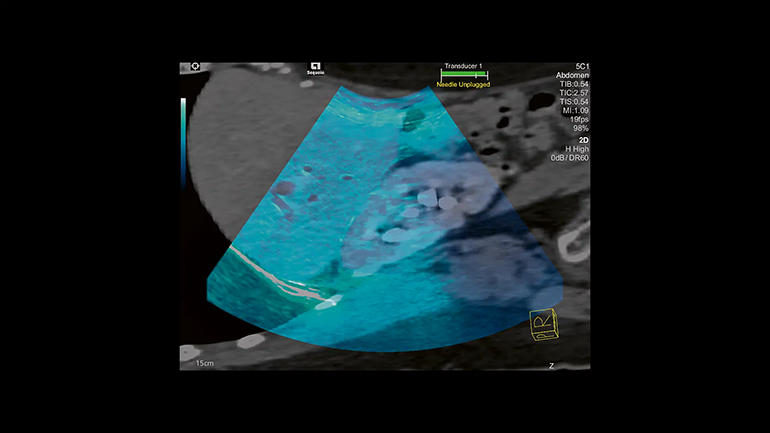

Технология суммации изображений

Эта технология в реальном режиме времени позволяет суммировать УЗ-изображения с диагностическими изображениями, полученные при использовании других диагностических методов визуализации (КТ, МРТ к примеру) для повышения надежности визуализации при сложных интервенционных процедурах.

Технология Fusion Эта технология позволяет суммировать изображения, полученные при работе с разными диагностическими модальностями для повышения надежности визуализации при сложных интервенционных процедурах.

Etrax Технология наведения биопсийной иглы Etrax позволяет отслеживать положение кончика иглы и повышает надежность нацеливания на труднодоступные поражения при сложных интервенционных процедурах.